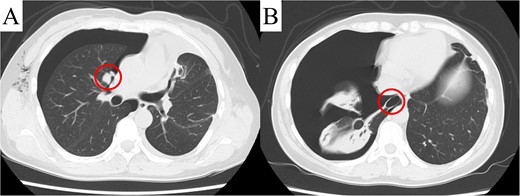

Despite a mild right pneumothorax on admission, the patient underwent a safe operation with chest drainage for the right pneumothorax. Intra-operative findings revealed a bulla at the apex of the left lung and unexpected pleural dissemination (Fig. 3A and B). Therefore, we performed a pulmonary metastasectomy and a pleural biopsy with bullectomy for diagnostic purposes. The patient was discharged without complication or exacerbation of the pneumothorax. However, recurrence of the right pneumothorax was observed four days after discharge, and surgery was scheduled. CT revealed a pleural dissemination nodule in the right hilar area and a bulla in the right lower lobe, in addition to the right pneumothorax (Fig. 4A and B). Intra-operatively, we identified a pleural dissemination nodule in the right hilar area with moderate air leakage, and resection was performed (Fig. 5A). The bulla in the right lower lobe was also resected (Fig. 5B).

Computed tomography revealed a pleural dissemination nodule in the right hilar area (A) and a bulla in the right lower lobe (B). The findings are indicated by circles.